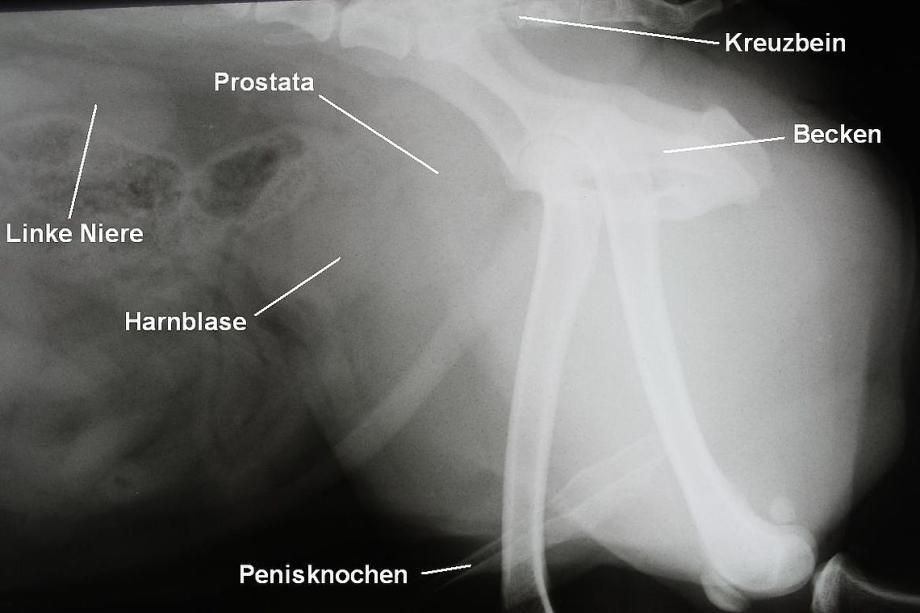

Blase und Harnröhre werden mittels einer normalen Röntgenaufnahme beurteilt. Hier wird insbesondere die Möglichkeit einer Verlegung der Harnröhre durch einen Stein untersucht; ausserdem können die Region von Lendenwirbelsäule und Beckenkanal beurteilt werden - diese zwei Bereiche können bei Tumoren der Prostata von Ablegern befallen werden. Die Röntgenaufnahme zeigt aber keine Auffälligkeiten ausser einer vergrösserten Prostata.